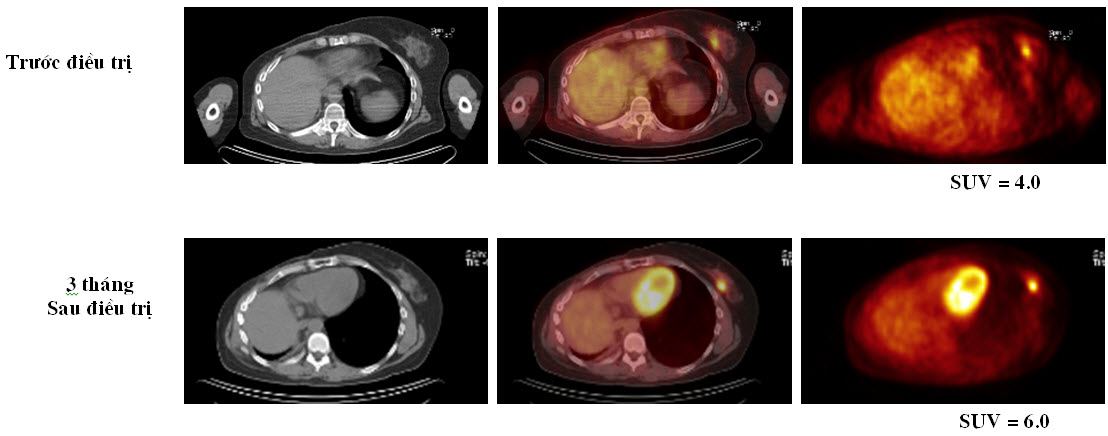

Trong điều trị ung thư vú, hóa chất tân bổ trợ được sử dụng để cải thiện ung thư vú nguyên phát cùng khả năng cắt bỏ và khả năng phẫu thuật bảo tồn vú. Đánh giá đáp ứng sớm với phác đồ hóa chất đã lựa chọn là cần thiết nhằm thay đổi phác đồ điều trị khác hay tiếp tục điều trị phác đồ cũ. Thông tin về lâm sàng và chẩn đoán hình ảnh thường không chính xác và phải mất thời gian lâu mới phát hiện ra sự suy giảm kích thước khối u. Điều trị hiệu quả tác động đầu tiên đến quá trình trao đổi chất, sau đó làm giảm kích thước của u. Vì PET/CT là kỹ thuật có độ tin cậy cao để đánh giá mức độ đáp ứng với hóa chất hơn các phương pháp thông thường.

Hình 5. Bệnh nhân nữ 51 tuổi với ung thư vú thứ phát ở bên trái đã được điều trị hoá chất. Trên hình ảnh PET không thấy biểu hiện đáp ứng, kích thước u không thay đổi đáng kể. Bệnh nhân đã phải thay đổi cách điều trị.